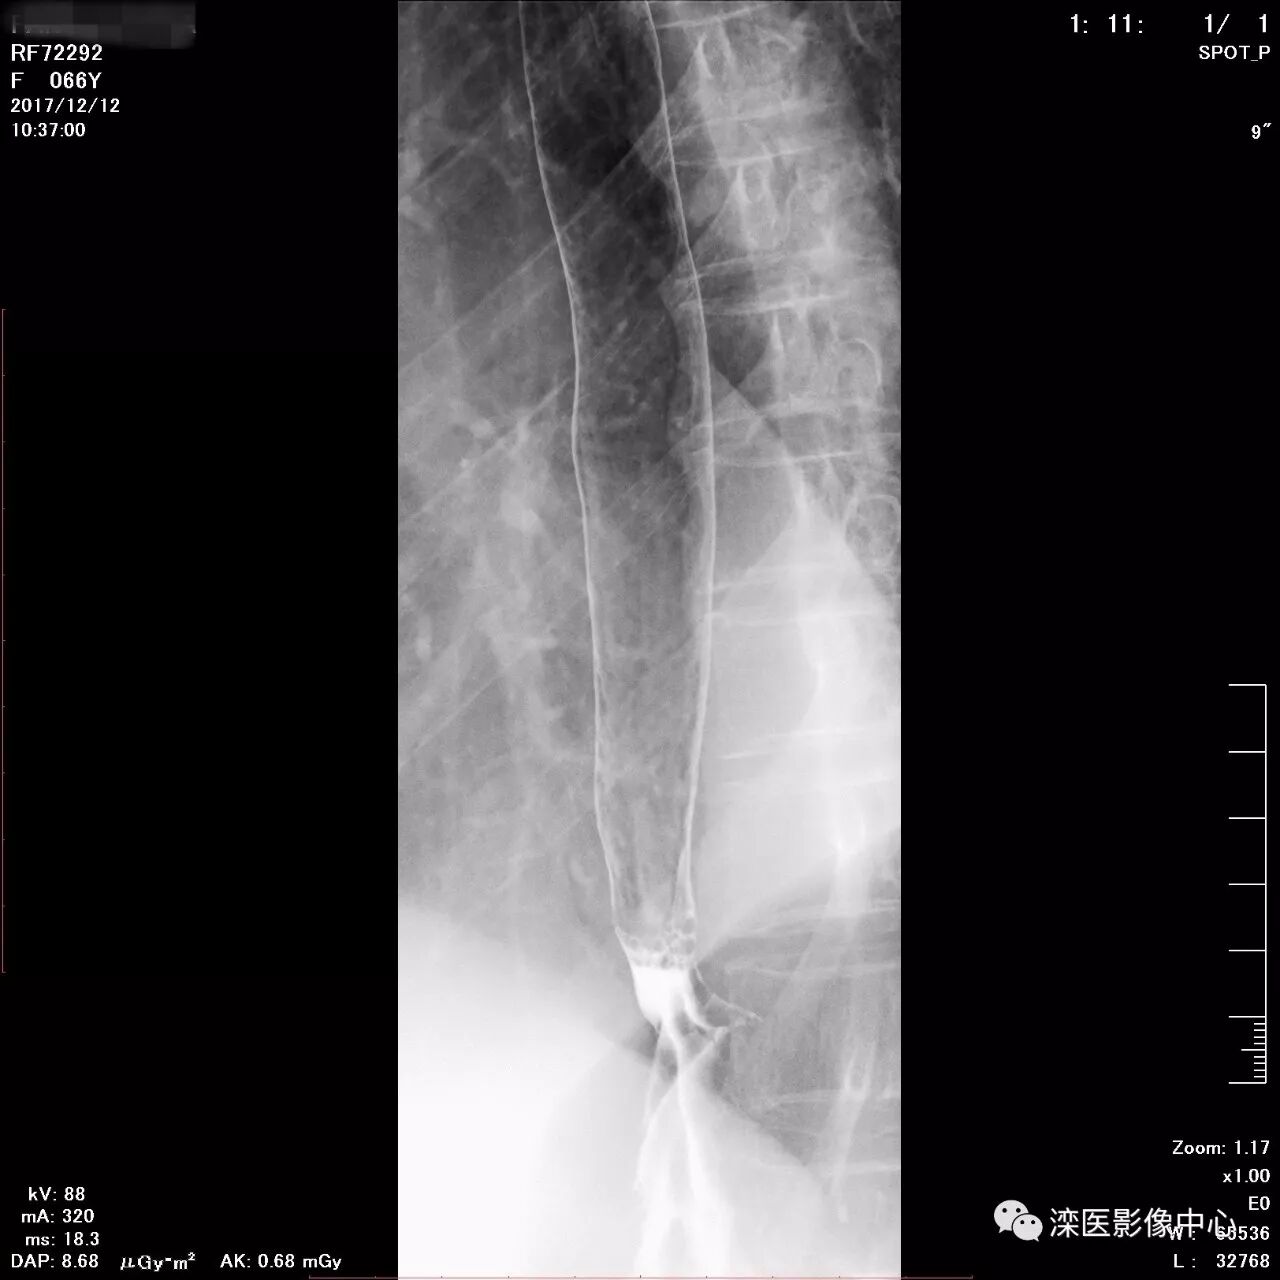

正位,显示食管、贲门及喉咽部的粘膜像)

(左前斜位,显示食管、贲门的粘膜像

(右前斜位,显示食管、贲门的粘膜像)

(以上图像是患者立位+卧位,通过变换体位,多角度显示了贲门胃底、胃体、胃大弯、胃小弯、胃窦、幽门及十二指肠球部、降部、水平部、升部的粘膜像和充盈像。本例患者女性,66岁,此次检查可以清晰显示胃小区结构,检查中发现患有慢性胃炎、胃下垂、十二指肠降部憩室)